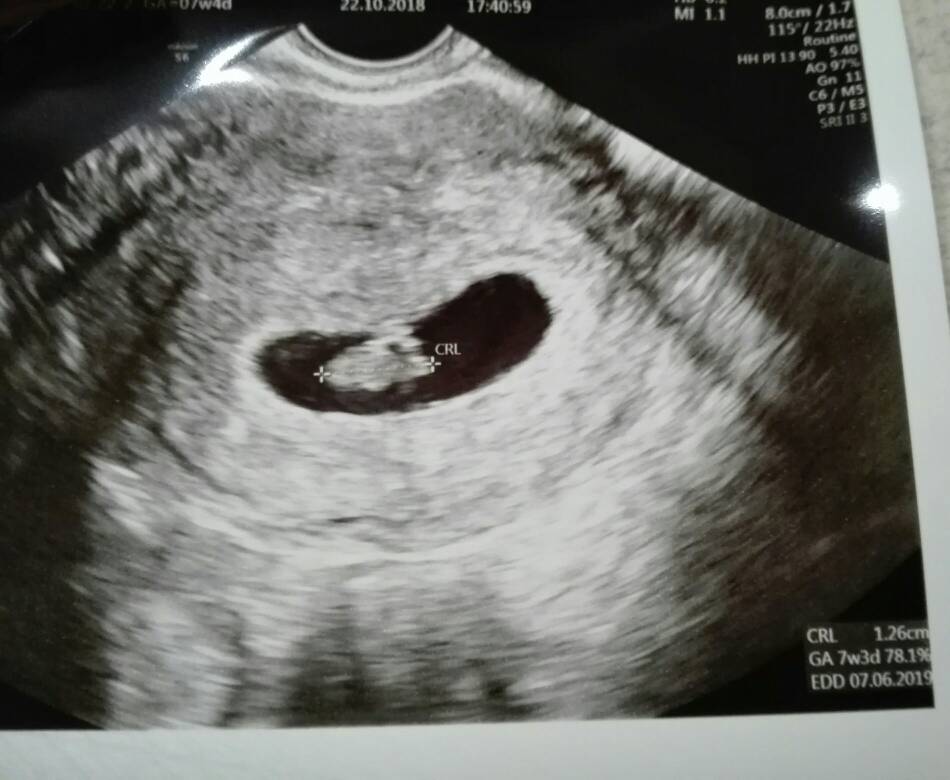

Cześć dziewczyny [emoji7] jestem przeszczesliwa, moja dzidzia ma 1,26cm i pieknie bijace serduszko [emoji7][emoji7]

Mam porobic badania i za niecale dwa tygodnie kolejna wizyta [emoji7]

Wzruszylam sie jak pokazalam mlodemu zdjecie usg jak wypytywal gdzie dzidzius jak duzy jest i co tam w brzuchu robi [emoji28] [emoji7] a potem tz pokazywał gdzie jest dzidzia [emoji7][emoji173][emoji173]Zobacz załącznik 909926